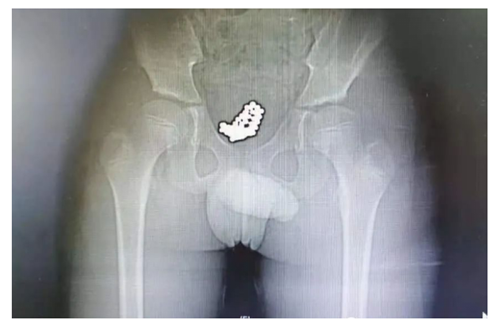

看急诊。医生询问病情时,发现小奇全程都低着头,好像试图躲避医生和家长的眼神,只说自己头天下午去游了泳,其他一概支支吾吾、避而不答。随后,医生给他拍了一个CT,一拿到片子就大致猜到是怎么回事了。“从片子可以清晰看到,他的膀胱里充满了一颗颗小珠子,直径大约5毫米 ,估计是不久前塞进去的!”泌尿外科副主任医师刘明分析。

患者的CT片